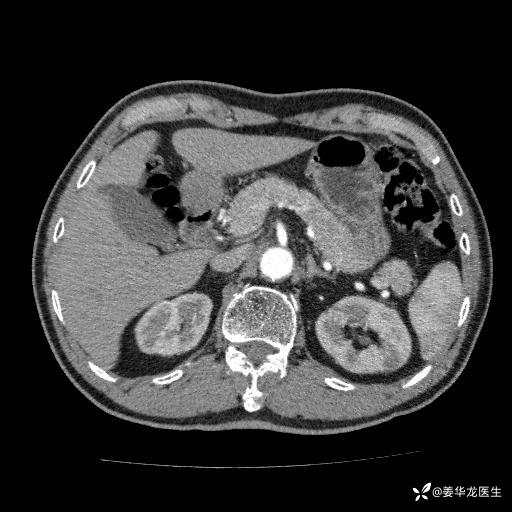

左肾中心型肾门部肿瘤39mm×34mm×36mm,右肾GFR25ml/min,部分切还是全切?

患者75岁老年男性,体重50kg,无高血压、肾病、糖尿病等基础病,检查发现左肾中心型肾门部肿瘤,右肾GFR只有25ml,无肉眼血尿,无镜下血尿。入院验血常规检查均正常,包括肾功能,肌酐102.7umol/L.

二、左肾肿瘤与左肾集合系、左肾动静脉关系密切,左肾部分切除术可行吗?成功率有多大?成功部分切后,肾功能还有多少?

三、患者无任何基础病,为什么右肾GFR只有25ml/min,反尔有肿瘤的左肾GFR达38.8ml/min?